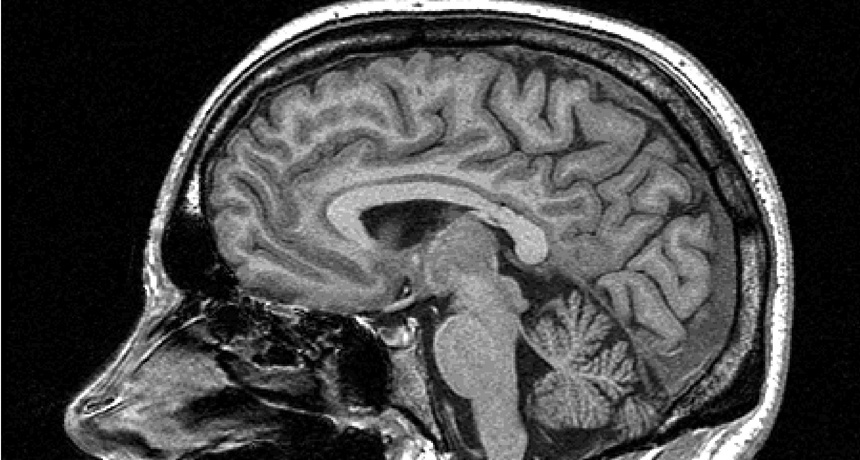

фМРТ сканирование мозга сон сновидения research

фМРТ-визуализация активности мозга. Источник: Philips